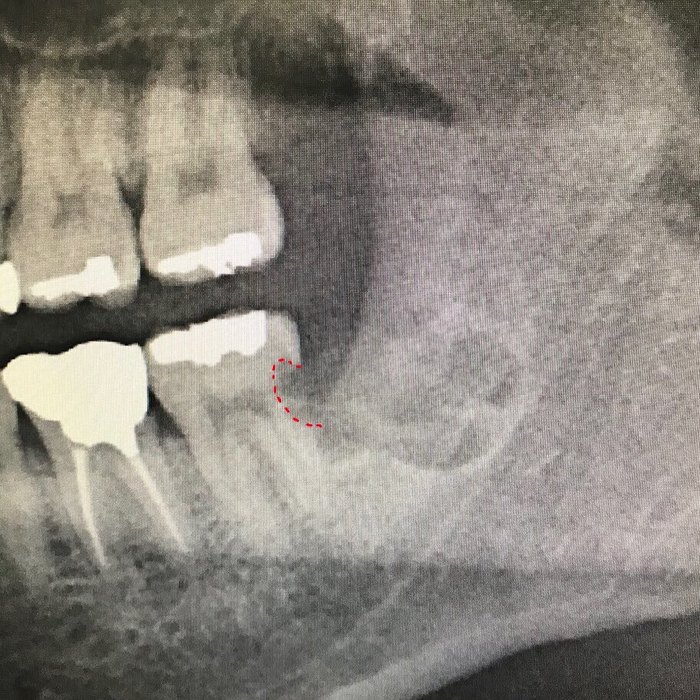

Вот наглядный пример такого того, к чему может привести несвоевременное удаление зуба мудрости. И не болит же! Мужчина обратился совсем с другой проблемой, обнаружили случайно, когда сделали панорамный снимок зубов.

Из-за неправильного положения 8ки на контактной поверхности зуба номер 7, образовалась достаточно глубокая кариозная полость, уходящая глубоко под десну.

Зуб мудрости успешно удален, а вот семерка на очереди… (8ка поделена на три фрагмента — коронковая часть и два корня)

Казалось бы, нормальный зуб. «Ну кариес, вон, пломба стоит одна, поставить еще одну, делов-то!». Все не так просто, так как кариозная полость уходит глубоко под десну, подобные зубы лечению не подлежат. Почему? Потому что при постановке пломбы, обработанная полость должна быть сухой. Добиться этого при таком поражении невозможно. Как минимум из-за того, что в десне содержится «десневая жидкость», которая постоянно будет подтекать в эту область.

Что же делать? Вариант один — удаление зуба и имлантация. Увы.